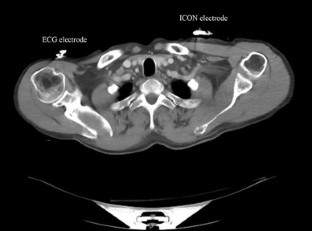

Fig. 1

Fig. 2

Fig. 3

Fig. 4